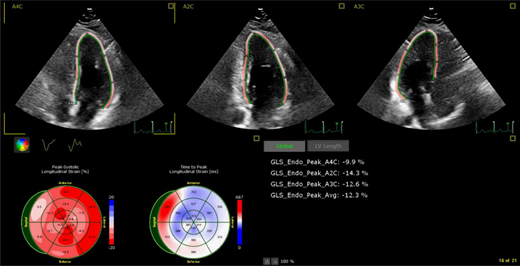

Although most screening is performed using echocardiography, CMR can more precisely quantify left ventricular systolic function among survivors with borderline left ventricular EF (LVEF) by echocardiography (50%-59%).23  CMR also more accurately quantifies left ventricular mass, which can be abnormally low in approximately half of childhood cancer survivors with abnormal EF,23  and provides tissue characterization (Figure 5). Low left ventricular mass may have prognostic value among these survivors as it has been shown to be associated with an increased risk for adverse cardiovascular events among survivors of adult-onset cancer.24  In addition, approximately one-third of childhood cancer survivors may have right ventricular dysfunction, and CMR is the preferred method to evaluate the right ventricle.25

Figure 5.

Example of cardiac magnetic resonance imaging revealing mildly reduced ejection fraction (52%; lower end of normal being 58%) with mid-myocardial delayed enhancement indicative of cardiac fibrosis (white arrows) in a long-term non-Hodgkin lymphoma survivor >30 years after doxorubicin-based chemotherapy who presented with premature ventricular contractions.